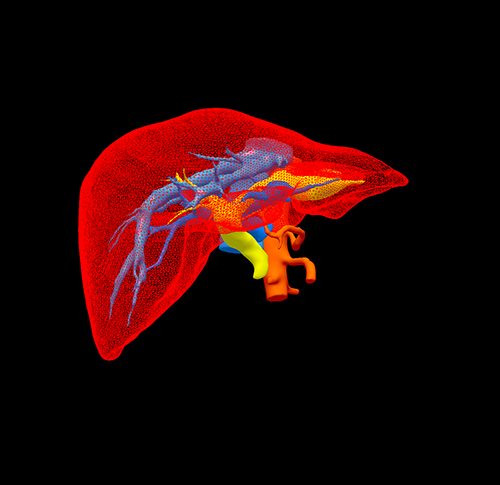

左肝管结石--左肝叶切除